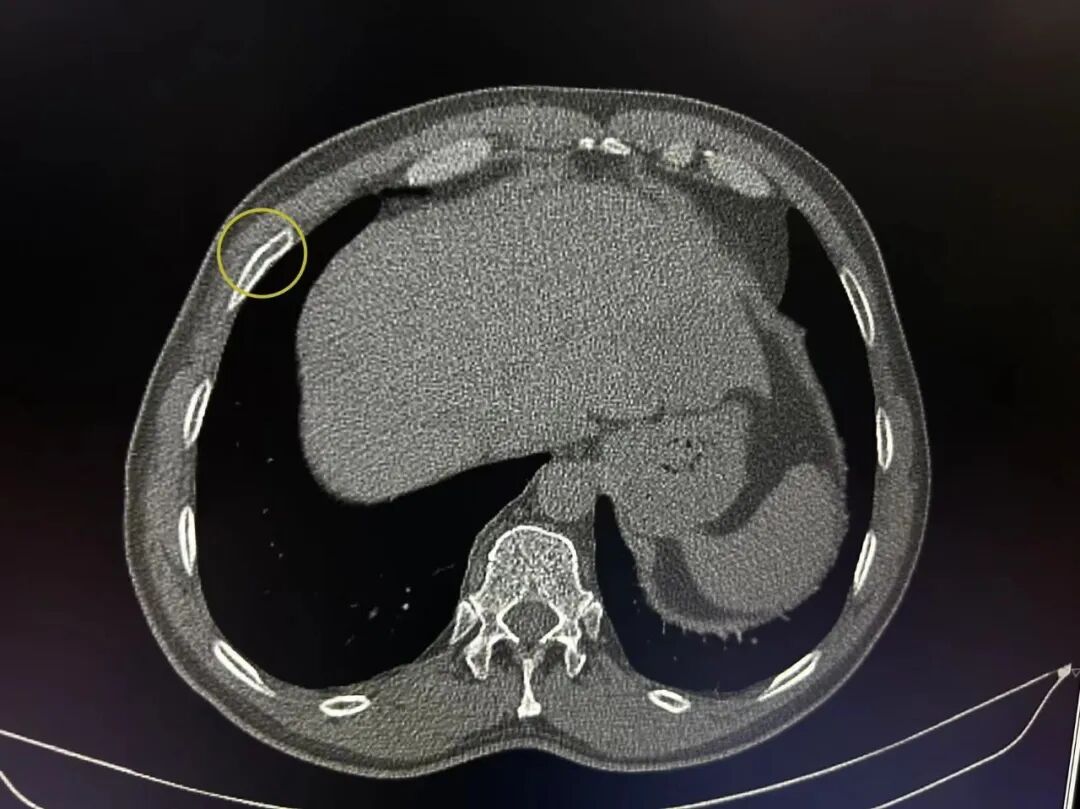

案例3、44岁的患者肋骨骨折复查平片未能明确显示骨折部位,CT扫描显示左侧第五前肋骨皮质不规则、边缘骨痂形成。